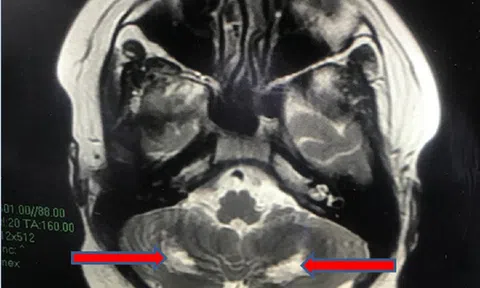

Bé trai 13 tuổi bị tổn thương não hậu COVID-19

Bệnh viện Nhi đồng Thành phố (TP.HCM) vừa cứu sống một bệnh nhi 13 tuổi mắc COVD-19 cấp tính, sau đó xuất hiện hội chứng viêm đa hệ thống, tổn thương não.